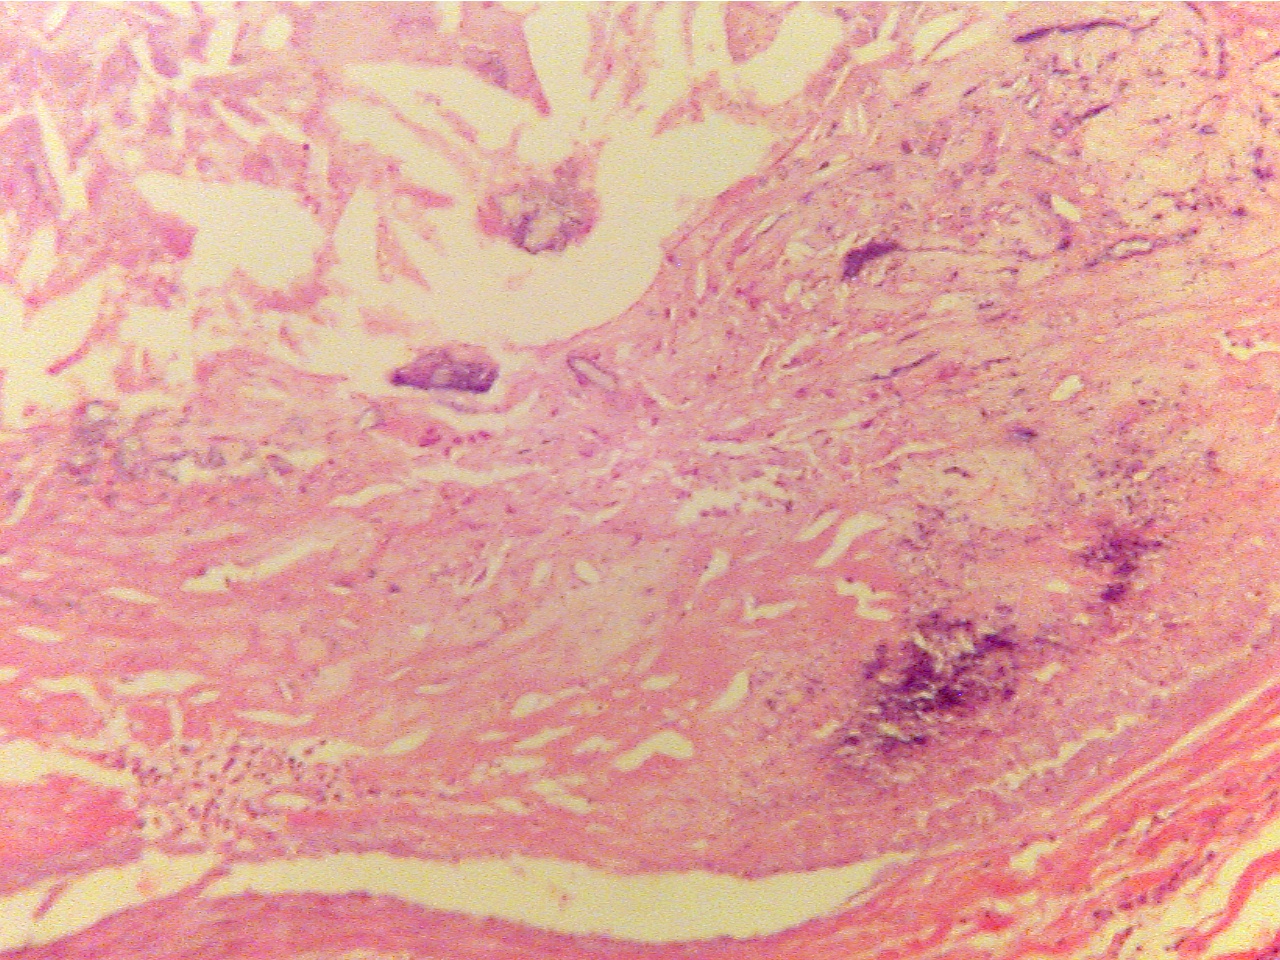

Advanced lesion (100X2.0 - b2)

Externa at left, lumen at right

Lumen at far lower left corner, lesion of mixed

substances and cells fills center region